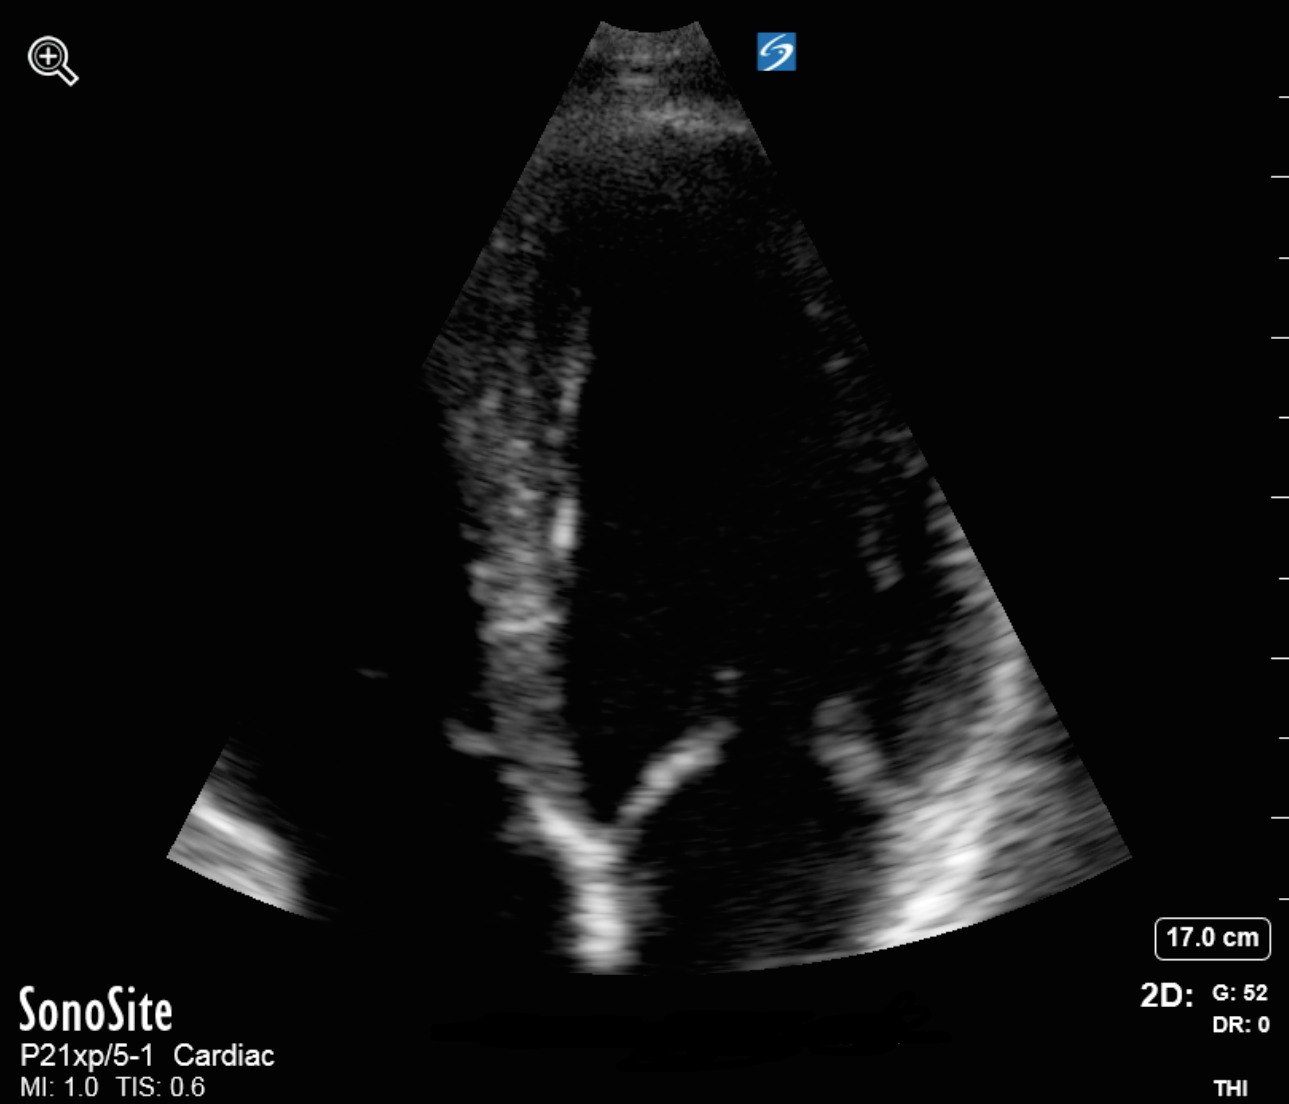

二尖瓣心尖缩放图像